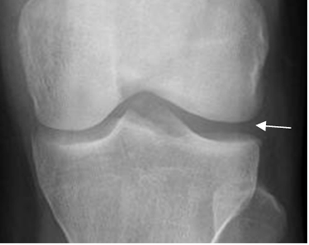

En la Rx simple puede encontrarse aumento del compartimiento afectado. (Fig 189).

Fig 189. Menisco discoide.

Rx AP. Aumento del espacio femorotibial lateral, por asociación con menisco discoide.